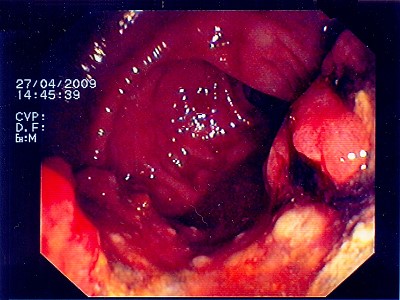

Abb. 4: Bei diesem bösartigen Gebilde handelt es sich um einen Krebstumor, der das Innere des Darmes nahezu vollständig verschlossen hat. Abb. 4: Bei diesem bösartigen Gebilde handelt es sich um einen Krebstumor, der das Innere des Darmes nahezu vollständig verschlossen hat.